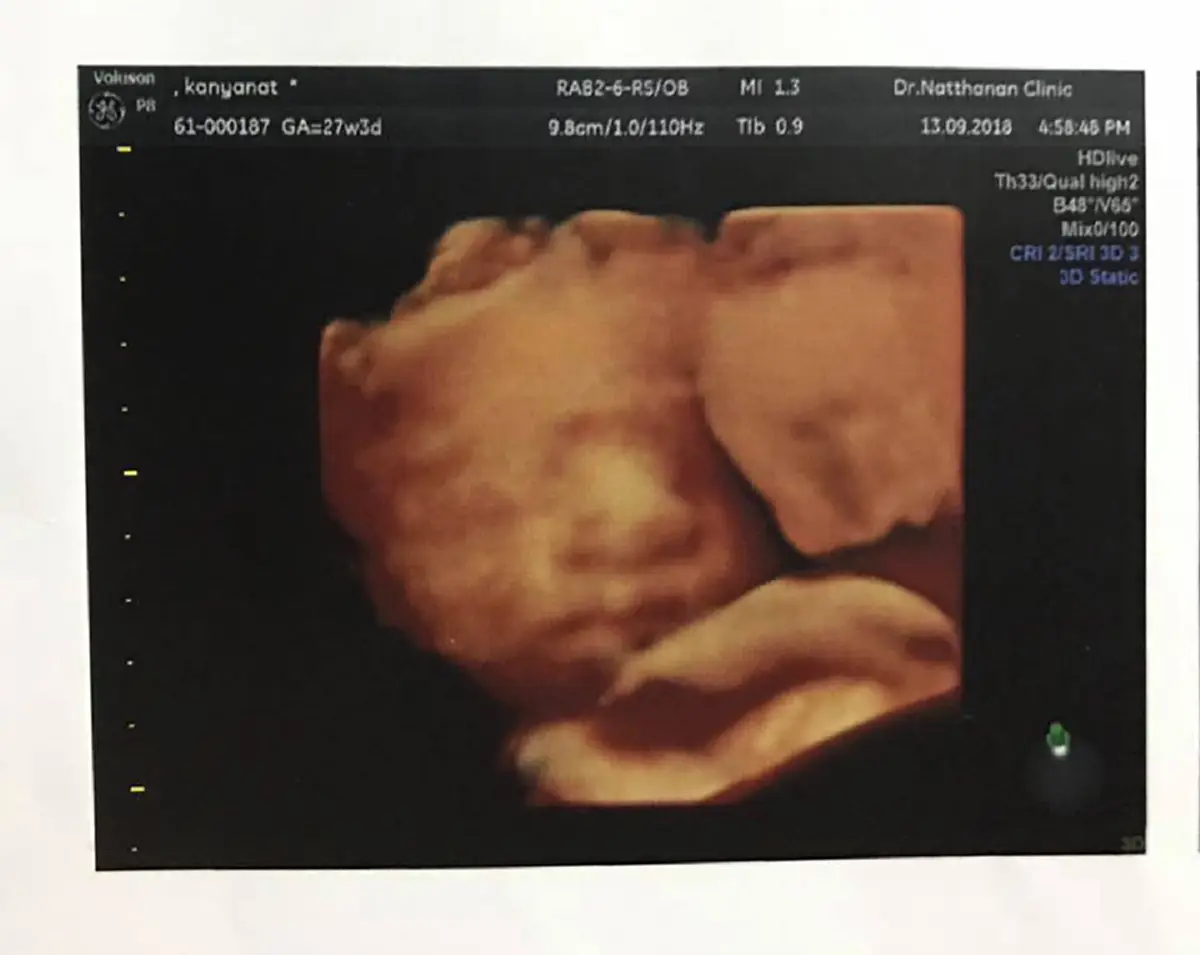

"มีเรื่องมาเล่าสู่กันฟังครับ เนื่องจากแฟนผมเองท้อง ได้ไปฝากท้องที่ #คลินิก.พญ.ณัฐนันท์ ช่วงเราได้รับการรักษาที่ดีตามแผนการของการตั้งครรภ์ ช่วงการรัษา 2-5 เดือนการตรวจก้อเป็นไปตามปกติดีแข็งแรงทั้งแม่และน้อง แต่แฟนเราจะมีอาการ ขาบวม หายใจติดขัด เหนื่อยง่าย ในช่วง 7-8 เดือน เราจึงไปพบหมอ #ณัฐนันท์ เพื่อตรวจว่ามีอาการของครรภ์เป็นพิษไหม คำตอบที่ได้จากหมอ บอกว่าไม่มีอาการผิดปก ทั้งแม่และเด็กปลอดภัย แข็งแรงน้ำหนักตามเกณฑ์ แฟนเราก็สบายใจขึ้น แต่หลังจากนั้นไม่กี่วันที่ไปรักษามา แฟนเราเริ่มมีอาการหนัก เหนื่อย หายใจแรง ปากเขียว เท้าบวม หายใจติดขัด เราจึงได้พาไปหาหมอที่ รพ.ชลบุรี สิ่งแรงที่หมอบอกคือ แม่กับน้อง โอกาสเสียชีวิตทั้งคู่ ต่อจากนั้นก้อตรวจเอ็กซเรย์ฉายแสง แต่ก่อนจะเข้าตรวจแฟนเรากลับไม่หายใจไปสักพัก ซึ่งมันก็ส่งผลต่อลูกแน่นอน เวลาต่อหมอที่ รพ.ชลบุรี ก็ได้ผ่าตัดเอาลูกเราออก เพื่อที่จะให้รอด1ชีวิต แต่อย่างว่าทุกอย่างมันสายเกินไป ร่างกายแฟนเราภายในมันเสียหายหนักมากเกินกำลังหมอที่จะรักษาช่วยชีวิตแล้ว ส่วนตอนนี้ลูกเราก็ยังอยู่ในตู้อบICUเด็ก มีอาการความดันต่ำ หายใจเองไม่ได้ต้องต่อท่อช่วยหายใจ หมอกำลังช่วยลูกเราเต็มที่อยู่ #ตอนนี้เราหวังให้ลูกเราแข็งแรงกลับมา เพราะแม่ของลูกเราก็เสียชีวิตไปแล้ว #มันเกิดคำถามใจว่า...